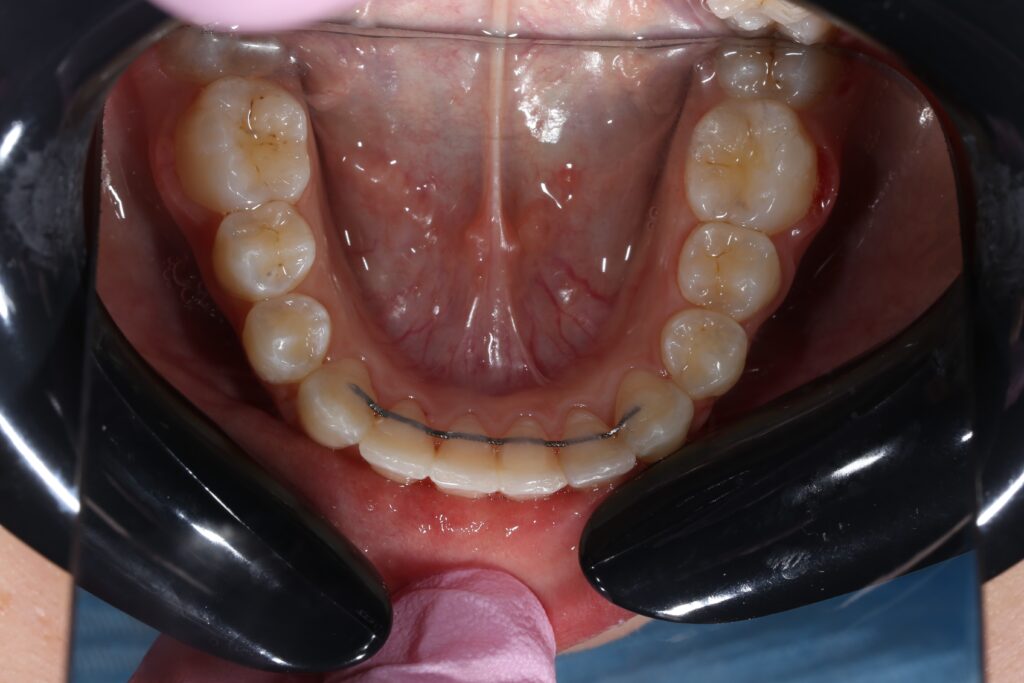

Ситуация до лечения

Жалобы: Пациентка обратилась с жалобами на неровное положение передних зубов.

Диагноз: дистальный прикус, сужение верхнего и нижнего зубных рядов, скученность фронтальной группы зубов на верхней и нижней челюсти.

пациент до лечения брекетами